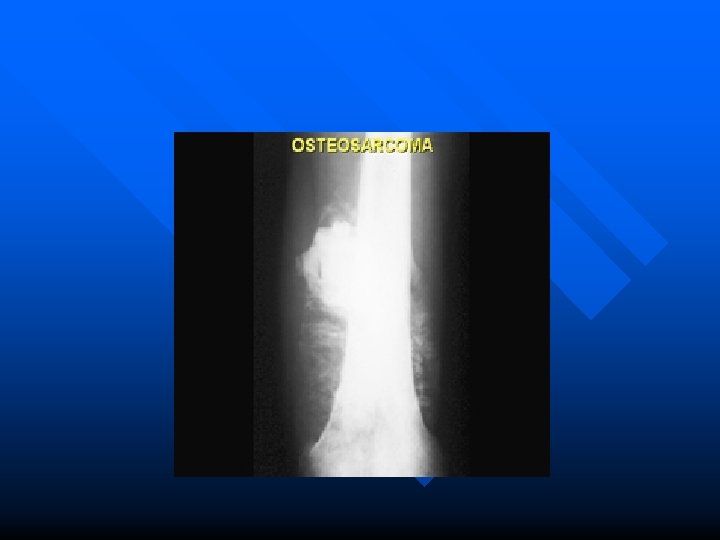

Tumors of the bone in plain photo Three important question requere to answered : 1. Neoplastic or infective 2. Benign or malignannt 3. Primary or secondary neoplasm. n

General principles of radiological diagnosis of bone tumors : n consider the age of the patient and the clinical hystory. a. Lesion soliter or multiple Type of bone involved Position of the lesion within the bone : cortex, disphysis, metaphysis Plain film features : radioluscent focus, radioopaq, ground glass Margins of the lesion look like b. c. d. e.